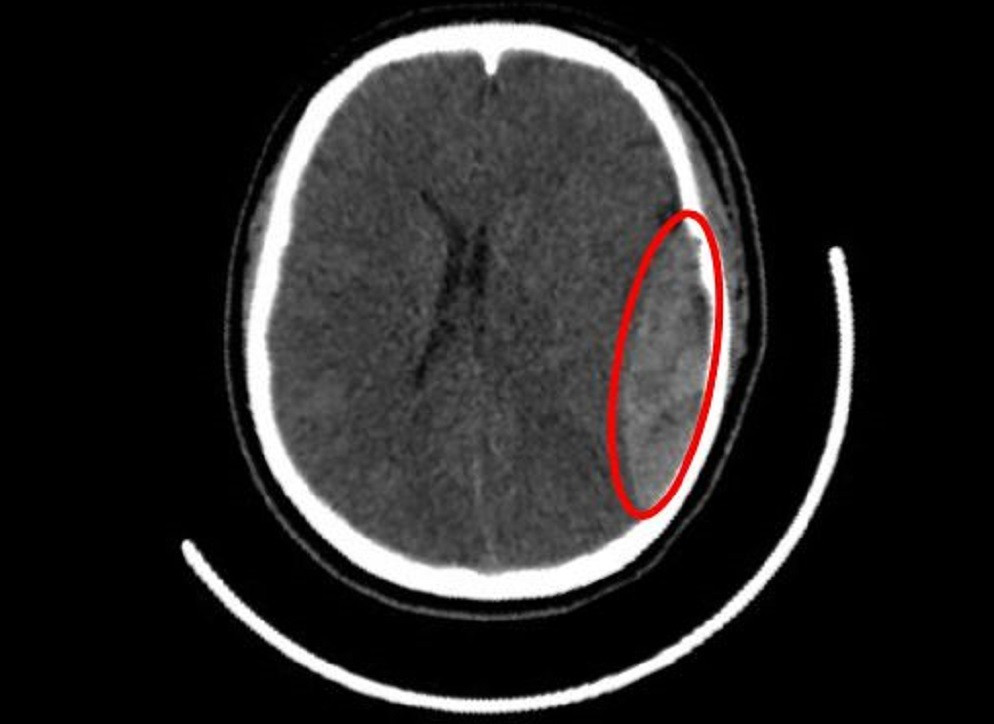

Hình ảnh kiểm tra ghi nhận vị trí nứt hộp sọ, máu tụ dưới màng cứng nữ sinh gặp phải

Tại khoa Cấp cứu, các bác sĩ ghi nhận bệnh nhân bị yếu nửa người bên phải, tri giác giảm còn khoảng 9–10 điểm Glasgow. Kết quả kiểm tra hình ảnh cho thấy, một khối máu tụ ngoài màng cứng ở bán cầu não trái lan xuống vùng thái dương, kèm theo nứt xương hộp sọ thái dương. Khối máu tụ có dấu hiệu tăng thêm, nghi do đứt động mạch màng não giữa – một vị trí chảy máu lớn và nguy hiểm.